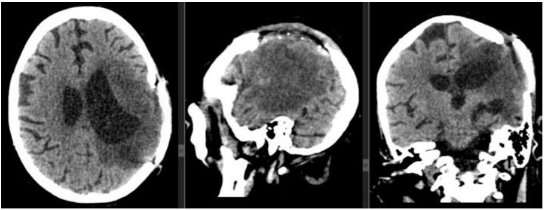

The second case is a 63-year-old male patient with a history of benign prostatic hyperplasia who underwent surgery in 2018. He debuted in January 2022 with associated gait instability, associated with intense, oppressive, holocranial headache, predominantly in the morning with little response to taking analgesics. No positive findings were found in the neurological physical examination.

In the emergency room, a simple head CT scan was performed, which showed mixed density images in the right fronto-parieto-temporal region, producing a mass effect on the ipsilateral lateral ventricle, as well as displacement of midline structures, surrounded by abundant perilesional edema.

After administration of contrast, the walls enhance intensely, appearing irregular and thickened (Figure 13).